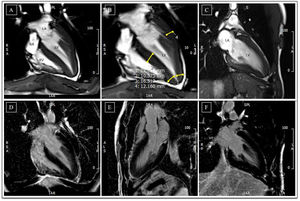

Cardiac magnetic resonance before detraining. (A-C) Cine steady state free precession sequences (in diastole) with overlapping echocardiographic findings – similar wall thicknesses, particularly in the LV apical segments. Long-axis horizontal views enable visualization of the apex, with a clearly abnormal cavity morphology, confirming the diagnosis of apical hypertrophic cardiomyopathy, mixed form, with an ‘ace of spades’ configuration; (D-F) delayed enhancement sequences showing absence of myocardial fibrosis. LA: left atrium; LV: left ventricle; RA: right atrium; RV: right ventricle.